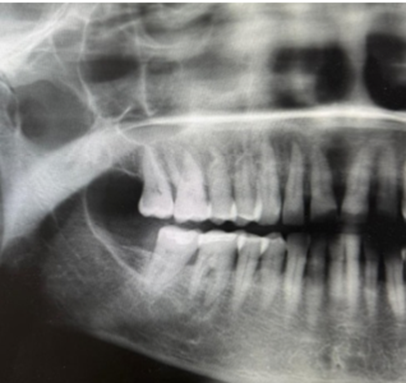

Radiographic findings observed from the initial panoramic image (Figure 3) included: (1) minor signs of pathology with widening of the periodontal ligament space of the tooth 1.4 and tooth 1.5; and (2) root resorption of tooth 1.4 and tooth 1.5. The crowns, pulpal and root canals of the teeth in the posterior right maxilla were seemingly within normal limits. Given that widening of the periodontal ligament space of the maxillary premolars in the absence of dental disease suggests an etiology distinct from that tooth.

Figure 3: Cropped and enhanced panoramic radiograph demonstrating mild widening of the periodontal ligament space and root resorption of teeth 1.4 and 1.5.